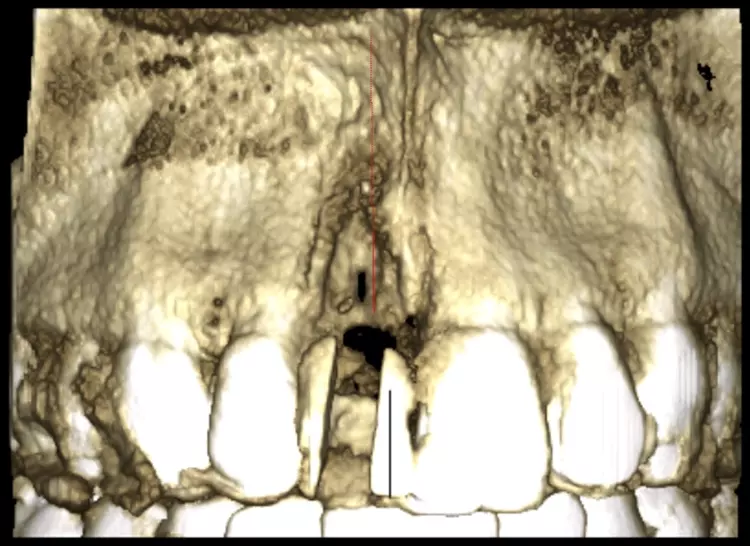

Im Sinne eines Backwardplanning wurde anhand eines Waxups die Marylandbrücke als auch die entsprechende Bohrschablone hergestellt. Nach eingehender präimplantologischer Diagnostik mittels Modellanalyse und digitalem Volumentomogramm (DVT) zeigte sich eine ausgeprägte bukkale knöcherne Fenestration (Abb. 8 und 10).

Nach einer viermonatigen Einheilzeit wurde im Rahmen der präimplantologischen Diagnostik ein DVT zur Überprüfung des Augmentationsergebnisses erstellt und die Implantatgröße festgelegt (Abb. 9 und 11). In Lokalanästhesie und unter Zuhilfenahme einer Bohrschablone erfolgte nach midkrestaler Schnittführung unter Schonung der Papillen die manuelle Insertion eines Straumann Bone Level Implantats mit den Maßen 4,1 x 10 mm RC (Straumann AG, Basel, Schweiz). Das Eindrehmoment betrug 35 Ncm.